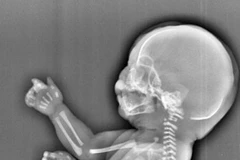

Một bà mẹ trẻ ở thành phố Yichang, tỉnh Hồ Bắc, miền Trung Trung Quốc đã buộc phải phá thai khi sau khi phát hiện ra thai nhi phát triển không bình thường.